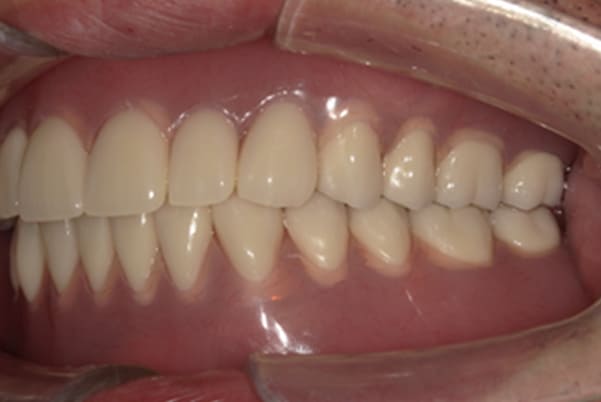

症例レポート[CASE.06]

- 男性(70代)

- 下歯がぐらぐらで抜けそうで痛い、何でも咬めるようにしてほしい

- 治療

- 上顎精密金属床部分入れ歯

- 下顎精密金属床部分入れ歯

- 陶材焼付鋳造冠 4歯

- 磁性アタッチメント 1歯

- 治療期間

- 約6か月間

- 費用

- 上顎精密金属部分入れ歯:55万円

- 下顎精密金属部分入れ歯:77万円

(治療用義歯含、咬合平面等修正) - 陶材焼付鋳造冠:16.5万円×3歯

(ミリング加工) - 陶材焼付鋳造冠:14.3万円×1歯

(ミリングなし) - 磁性アタッチメント:11万円×1歯

(白金加金)

合計:157.3万円(税込)

奥歯がなくなり放置されていたため、前歯に負担がかかり、歯周病も併発されており歯がぐらぐらでお痛みも伴う状態でした。

可能な限り残せる歯は保存し虫歯治療を行い、どうしても残せないお痛みの歯のみ抜歯を行いました。

陶材焼着付鋳造冠 ミリングラべット加工

残りの歯が少ない場合は、入れ歯が動きやすく、またご自身の歯にも負担がかかるため、残りの歯の被せ物、入れ歯ともに、歯に負担がかかることを最小限にした特殊な加工を行い、歯を長持ちさせる設計としました。

上の入れ歯

下の入れ歯

上の入れ歯は、治療用入れ歯において、前方に違和感を訴えられていたため、違和感のない範囲を治療用入れ歯で決定し、最後の入れ歯に反映することで、上下ともに初めての入れ歯でしたが、違和感を感じることなくご使用になられることが可能になりました。

このように、お一人おひとり、お口の中の感覚は個人差が非常に大きいため、治療用の入れ歯でかみ合わせ、見た目、違和感、お痛みなど、あらゆる項目をチェックし、ご意見をお伺いし、ご相談のうえ最終的な入れ歯の設計を行い作製することで、その方に合った入れ歯が出来上がります。

治療後に入れ歯を外した上顎

治療後に入れ歯を装着した上顎

治療後に入れ歯を外した下顎

治療後に入れ歯を装着した下顎